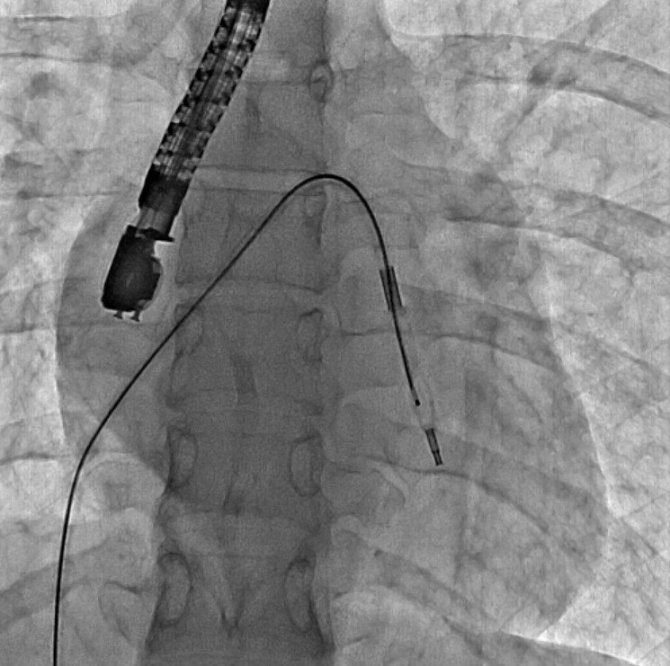

Eskişehir Şehir Hastanesi'nde ilk defa mitral balon operasyonu yapıldı. Operasyon, anjiyografi cihazı ile adım adım kaydedildi.

Eskişehir Şehir Hastanesi'nde Kardiyoloji Uzmanı Dr. Mehmet Özgeyik ve 4 kişilik ekibi tarafından ilk defa mitral balon operasyonu yapıldı. Türkiye'de az sayıda yapılan kalp kapağı balon işlemiyle yeni anne olmuş genç bir hasta sağlığına kavuştu. Bu sayede hastalar ameliyat olmaktan, ömür boyu kan sulandırıcı ilaçlar kullanmaktan ve metal bir kalp kapağı ile yaşamaktan kurtuluyor.

Gerçekleşen başarılı operasyon hakkında konuşan Kardiyoloji Uzmanı Dr. Mehmet Özgeyik, "Bu işlemi genellikle kalp kapaklarında ciddi darlık olan genç hastaların kişilere uyguluyoruz. Buradaki amacımız ameliyat olmadan, kasıktan küçük iki damar yolu açarak hastalarımızın kapak darlıklarını uzun süreli olarak genişletmeyi hedefliyoruz. Burada 23 yaşında yeni anne olmuş genç bir hastamıza müdahale yaptık. Hastamız ya kapak ameliyatı olacaktı ya da bu işlem sayesinde kapak darlığını aşmayı planlıyorduk. İşlem gayet başarılı oldu. Hastamızın kapak darlığını genişlettik. En azından 10-15 sene boyunca ameliyata gerek kalmadan hastamızı ilaç tedavisiyle takip etmeyi planlıyoruz" diye konuştu.

Cerrahi operasyonlar yerine mitral balon işlemiyle hastaları sağlıklarına kavuşturmak istediklerini aktaran Dr. Özgeyik, "Hastanemizde ilk kez yapılan bir işlem. Bu işlem için uygun hasta bulmak biraz zor oluyor çünkü çok sık yapılan bir işlem değil. Fakat gelecekte hasta portföyümüzün de artması ile birlikte daha sık yapmayı planlıyoruz. En azından hastalarımızı büyük bir cerrahi operasyona vermeden böyle küçük işlemlerle hayat kalitelerini artırmayı planlıyoruz. Hastamız ameliyata gitmiş olsaydı büyük bir operasyon geçirmiş olacaktı. Göğüs bölgesinde büyük bir kesiğe maruz kalacaktı. Aynı zamanda ömür boyu kullanması gereken farklı ilaçlar olacaktı. Hasta kendisine ait olmayan metal bir kapakla yaşamak zorunda kalacaktı. Biz bu işlemde hastaya kasıktan iki tane damar yolu açtık. Hastaya neşter ile kesme işlemi uygulamaktan kurtardık. Ayrıca hastanın hayatı boyunca kullanacağı kan sulandırıcı ilaçları uzunca bir süre ertelemiş olduk. En önemlisi de hastanın kendi kalp kapağını kullanmasını sağlamış olduk ve metal kapak yükünden kurtulmuş oldu" şeklinde konuştu.